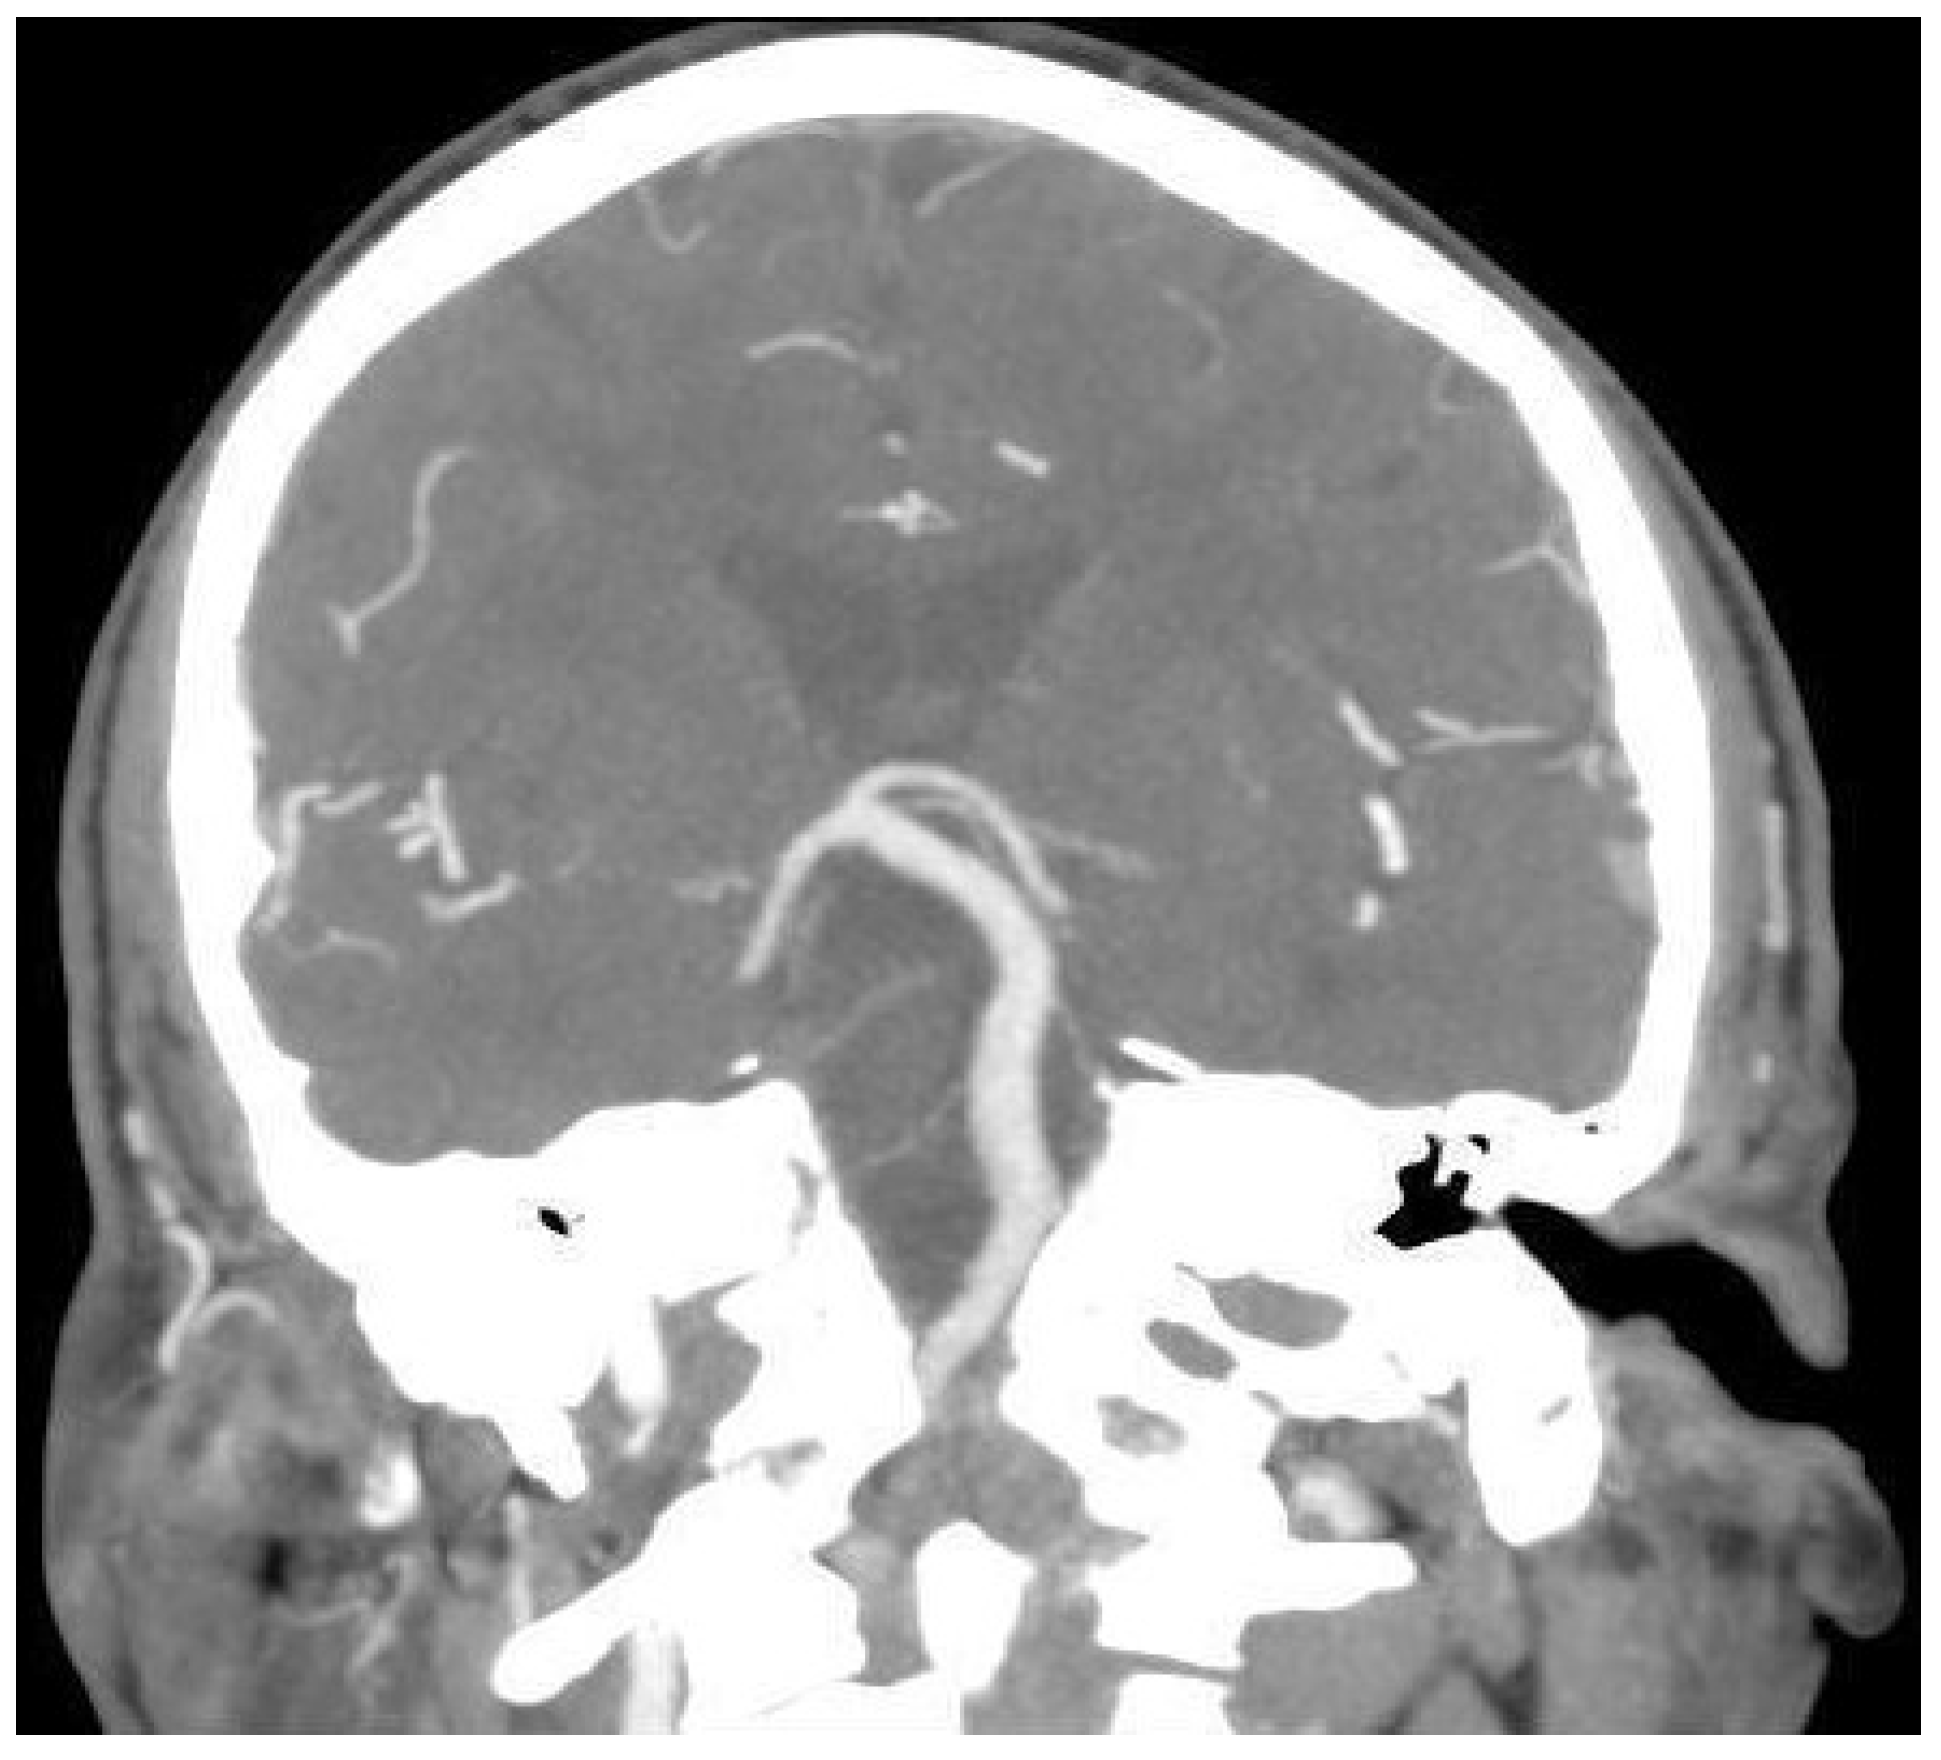

3.1.1. Case 1

3.1.2. Case 2

3.1.3. Case 3